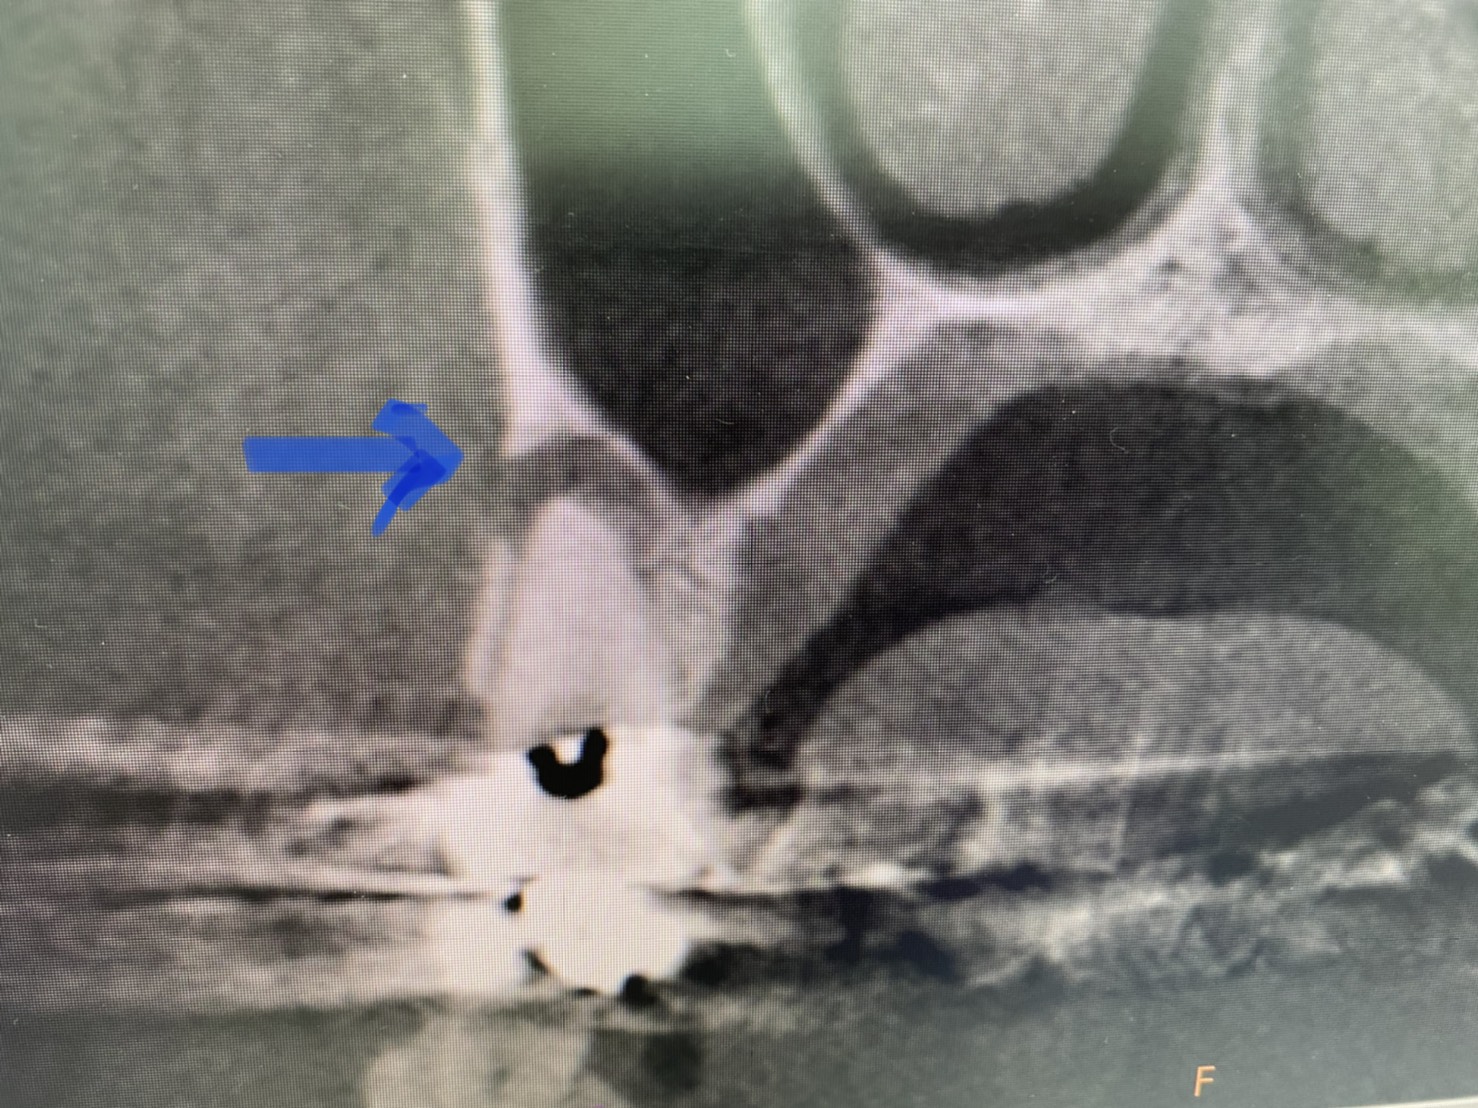

(2次元レントゲン画像) Before→After

画像見れば直ぐに気付くと思いますが、大きな根尖病巣が限りなく縮小し治癒しています

(After)